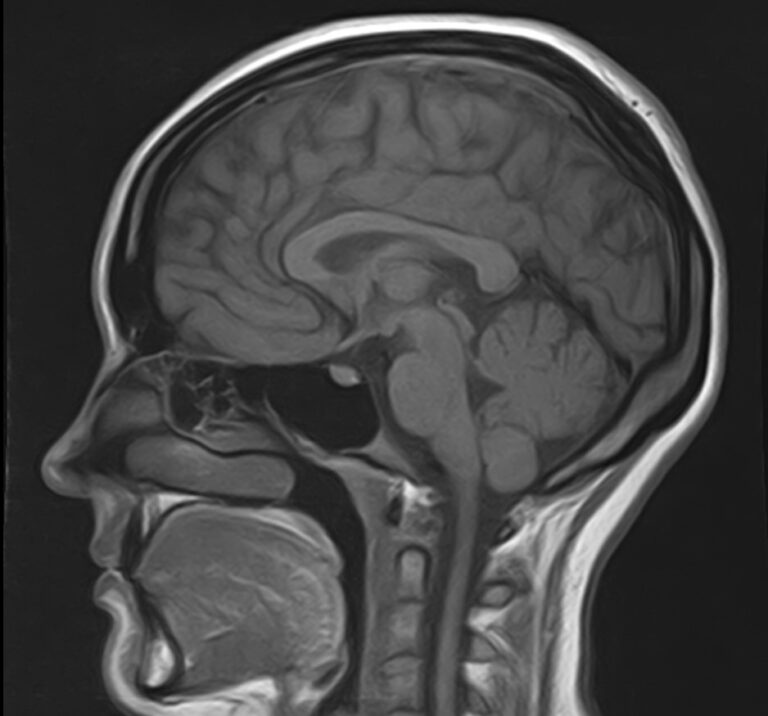

К центральной нервной системе организма относится головной мозг, расположенный в полости черепа, и спинной мозг, проходящий в спинномозговом канале позвоночного столба. В головном мозге находятся высшие центры управления всем организмом, спинной мозг имеет двусторонние связи с ними, то есть является проводником импульсов от периферии к головном мозгу и обратно.

Для диагностики заболеваний ЦНС в клинике «Доступная медицина» проводится комплексное обследование МРТ ЦНС (центральной нервной системы). Клиника укомплектована высокотехнологичным оборудованием, в частности, новейшим 32-канальным высокопольным томографом TOSHIBA VANTAGE TITAN 1,5 Тесла с высокой разрешающей способностью для точной диагностики заболеваний центральной нервной системы.

Комплексное обследование ЦНС выполняется как в стандартном режиме, когда не применяется использование контраста, так и с контрастным усилением. Для более точной диагностики некоторых патологий головного и спинного мозга внутривенно вводится контрастное вещество. С помощью контраста можно обнаружить опухолевые образования размером от 1 мм, демиелинизирующие процессы, дегенеративно-дистрофические заболевания, воспалительные процессы, сосудистую патологию.